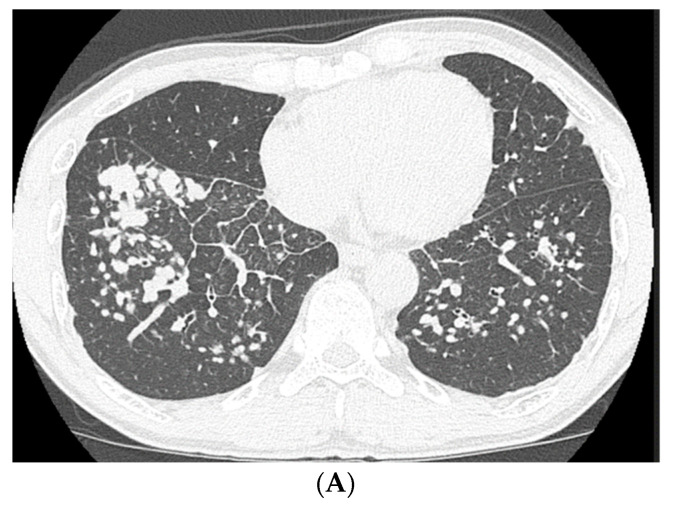

High-resolution computed tomography (HRCT) (Figure 2) showed well-defined multiple centrilobular and perilobular nodules, and thickening of the intralobular septa in the middle and lower zones of both lungs. No pleural effusion or mediastinal lymphadenopathy was observed.

Based on his history of occupational exposure and his clinical, radiological, and pathological findings, the patient was diagnosed with pneumoconiosis with a sarcoid-like reaction. He did not receive any medical treatment, such as corticosteroid administration; however, he stopped smoking and changed his occupation to avoid further exposure to dust. Two years later, the HRCT showed an increase in the nodular shadows (Figure 5A). However, the shadows were observed to have decreased after 5 years (Figure 5B).

The appearance of CBD in the radiological findings is similar to that of sarcoidosis, although mediastinal or hilar lymphadenopathy is less common and is usually seen in the presence of parenchymal opacities [ref. 18,ref. 19]. On chest CT, multiple nodules are the most common finding, often clustered around the bronchi and interlobular septa or in the subpleural region. Ground-glass opacities, bronchial wall thickening, and interlobular septum thickening may also be seen [ref. 18,ref. 19]. Compared with patients with sarcoidosis, extrathoracic manifestations, such as those observed in the eye, skin, heart, liver, and nervous system are rare in patients with CBD [ref. 18]. Further, there is little evidence of pneumoconiosis with a sarcoid-like reaction due to exposure to dust other than beryllium dust; however, similar findings have been reported in four out of five cases based on detailed clinical and radiological information [ref. 4,ref. 8,ref. 9,ref. 10,ref. 13]. Multiple nodules have also been observed in these four out of five cases [ref. 4,ref. 8,ref. 9,ref. 10,ref. 13], and mediastinal and hilar lymphadenopathy was observed in only one case [ref. 8]. Extrathoracic manifestations have not been observed. In our case, multiple nodules and thickening of the intralobular septa were the main radiological findings, and lymphadenopathy and extrathoracic manifestations were not observed. These findings correspond to pneumoconiosis with a sarcoid-like reaction.

The natural history of CBD has been variable, and the duration from beryllium sensitization to CBD development is reportedly 3.8 years (range, 1.0–9.5 years) [ref. 20]. The clinical course varies, and most patients experience a gradual deterioration in their condition; however, improvement may occur with the cessation of beryllium exposure [ref. 18,ref. 20,ref. 21]. Besides beryllium exposure, 18 months of toner dust exposure and 3 years of magnetite iron exposure have been shown to cause pneumoconiosis with a sarcoid-like reaction, without improvement in radiological findings despite administration of corticosteroid therapy [ref. 8,ref. 13]. By contrast, radiological findings of another individual exposed to aluminum dust for 15 years improved with corticosteroid therapy [ref. 4]. Further, there was no improvement in radiological findings in an individual exposed to glass wool fibers for 7 years, even after 4 years of exposure cessation [ref. 10]. However, in a case of pneumoconiosis with a sarcoid-like reaction in a limestone quarry worker with 8 years of employment, the radiological findings resolved 2 years after the relocation of his workplace [ref. 9]. In our case, the patient was engaged in underground construction as a civil engineer, with welding, cutting, and drilling of reinforced concrete and metals for 10 years, and the rapid progression of nodular shadows was observed over 2 years. Improvement in his condition was noted 5 years after exposure cessation. Due to limited evidence for pneumoconiosis with a sarcoid-like reaction, it is difficult to discuss the differences in the clinical course of the patients, and the effect of exposure cessation on the resolution of radiological findings. However, our findings largely suggest that cessation of exposure may improve progression of the disease [ref. 9].